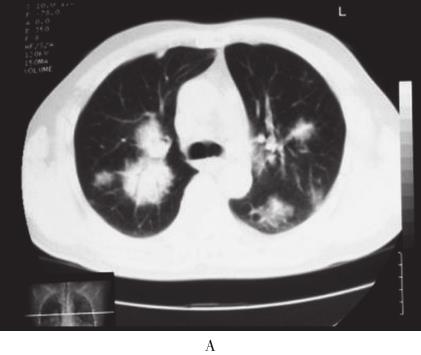

患者,男,56岁,因“活动后气短4年,加重3周”于2010年10月12日入院。入院前4年无诱因出现活动后气短,吸气时明显。3年前当地医院胸部CT检查示:双肺野内多个大小不等团片状密度增高影(图1A、B)。支气管镜下见:左上叶开口、右上叶开口及右下叶基底段开口处黏膜充血肿胀,管腔狭窄。支气管镜活检病理显示有大量淋巴细胞浸润。抗感染治疗后症状稍缓解。入院前1年上述症状加重,胸部CT示:双肺多发结节状、团块状病灶(图1C、D)。CT引导下肺穿刺活检病理示有大量淋巴细胞及浆细胞浸润,血管扩张充血,炎性渗出。诊断为双肺多发炎性肉芽肿,具体治疗不详。入院前2个月出现反复右侧鼻腔少量出血。入院前3周活动后气短加重,拟诊“双肺多发阴影性质待查”收入院。病来无发热、盗汗、咯血、胸痛、皮疹、关节痛。患者4年间多次在当地医院就诊,“怀疑肺结核、肺真菌病及肉芽肿病”,经验采用抗结核、抗真菌等治疗,具体治疗方案及疗程患者及家属叙述不清,疗效不佳。入院前半年,出现乏力、食欲下降,体重减轻4~5kg。

图1 胸部CT

A、B:2007年4月胸部CT示双肺野内多个大小不等团片状高密度.C、D:2009年10月胸部CT示双肺多发结节样、团块样病.E~G:2010年10月胸部CT示右肺下叶巨大团块状类软组织密度影,双肺弥漫性团片状浸润及实变影,纵隔内多发肿大淋巴结;胸片示右下肺团块影,双肺多发结节影